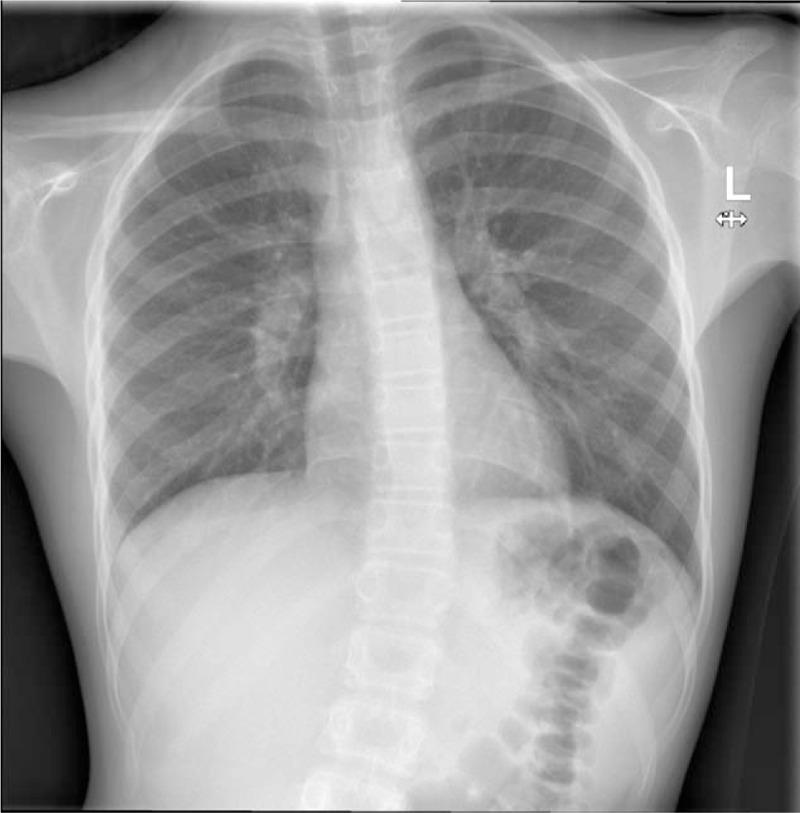

We describe the unique case of a child with pneumonia presenting with acute scoliosis and abdominal pain, without any typical features of the disease.A 10-year-old girl presented to the emergency department on 3 consecutive days with right-sided abdominal pain. There were no associated features, in particular, no fevers or respiratory symptoms. On the first 2 presentations, observation,examination, and blood test findings were unremarkable. Chest x-ray and abdominal ultrasound were also normal. On the third presentation a marked scoliosis was noted and abdominal examination revealed right-sided tenderness with rebound. The patient was admitted and a computed tomographic scan of the abdomen arranged. Unexpectedly, this revealed a right lower lobe pneumonia and associated pleural effusion. Despite treatment, the parapneumonic effusion enlarged rapidly and she developed respiratory distress, necessitating transfer to a tertiary centre.The diagnosis of pneumonia can be challenging because of a lack of respiratory signs, the masking of systemic features by antipyretic effects of first-line analgesics, and a high rate of false-negative chest radiographs. The development of acute scoliosis should lead the clinician to strongly consider pneumonia in such circumstances.

我们描述了一例独特的病例,一名患有肺炎的儿童出现急性脊柱侧弯和腹痛,无该疾病的任何典型特征。一名10岁女孩连续三天因右侧腹痛到急诊科就诊。无相关特征,特别是无发热或呼吸道症状。在前两次就诊时,观察、检查及血液检查结果均无异常。胸部X光和腹部超声也均正常。第三次就诊时发现明显的脊柱侧弯,腹部检查显示右侧有压痛及反跳痛。患者入院并安排了腹部计算机断层扫描。出乎意料的是,扫描显示右下叶肺炎及相关胸腔积液。尽管进行了治疗,肺炎旁积液仍迅速增大,她出现了呼吸窘迫,因此需要转至三级医疗中心。由于缺乏呼吸道体征、一线镇痛药的退热作用掩盖了全身特征以及胸部X光片假阴性率高,肺炎的诊断可能具有挑战性。在这种情况下,急性脊柱侧弯的出现应促使临床医生高度怀疑肺炎。